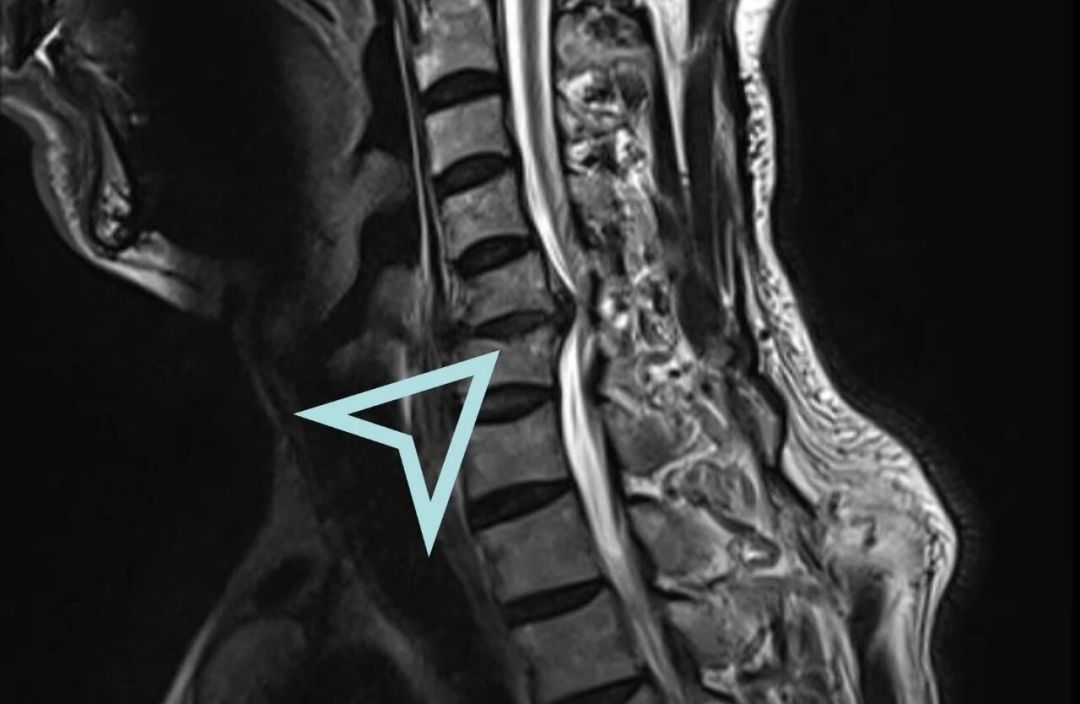

立即安排颈椎MRI检查让病灶“无所遁形”

检查结果实锤!李先生颈椎椎管狭窄、脊髓受压明显,确诊为脊髓型颈椎病——颈椎病里的“狠角色”!

脊髓型颈椎病是颈椎病中最严重的类型之一,是由于颈椎退变导致椎间盘突出、骨赘增生、后纵韧带肥厚等压迫供应脊髓的血管,从而出现颈脊髓损害的颈椎疾病。其主要症状包括四肢麻木、无力,以及大小便功能障碍等。脊髓型颈椎病好发于中老年人,且男性居多,因保守治疗效果差,常需要手术治疗。

其症状多为四肢疼痛、麻木无力,足踩棉花感,走路易跌倒等。病情比较轻的会影响生活及工作,病情严重的可能会出现大小便及性功能障碍,甚至四肢瘫痪。